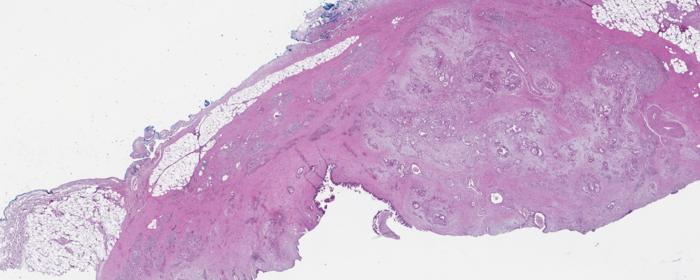

Scientists at the Van Andel Institute in Grand Rapids, Michigan, have achieved a groundbreaking advancement in the early diagnosis of pancreatic cancer through the development of a novel method for identifying and classifying cancer cell subtypes. This innovative technique revolves around the analysis of glycans—sugar molecules that adorn the surfaces of cells and play crucial roles in cellular communication and recognition. Pancreatic cancer, notorious for its lack of early symptoms, poses significant challenges for diagnosis and treatment. The new research promises to provide insights into the precise nature of pancreatic tumors by examining the unique glycan signatures present in these cells, paving the way for tailored therapeutic approaches.

The method, known as multiplexed glycan immunofluorescence, represents a significant technological leap. By utilizing advanced imaging techniques and sophisticated software, researchers can effectively capture the specific combinations of glycans associated with various pancreatic cancer cell subtypes. Each subtype of cancer cell often exhibits distinct glycan profiles that can provide valuable information about the tumor’s characteristics and potential treatment responses. This personalized approach holds the potential to enhance diagnostic accuracy and improve outcomes for patients suffering from pancreatic cancer.

The glycan signatures central to this research were identified by analyzing tumor tissues collected from patients. Following this initial discovery, the team refined their approach to detect glycans that are secreted into the bloodstream by cancer cells. This methodological refinement is crucial because the ability to perform blood tests is significantly less invasive for patients compared to surgical biopsies. As glycan analysis becomes a standard element of diagnostic procedures, patients may experience a more patient-friendly pathway to early detection and diagnosis.

Pancreatic cancer researchers face myriad challenges, not least of which is the intrinsic complexity of pancreatic tumors, which can encompass multiple subtypes of cancer cells coexisting in a single tumor mass. The presence of these diverse cell populations complicates treatment decisions, as different cells may respond variably to standard therapies. The new glycan identification method promises to simplify this complexity by providing a clearer picture of the cellular dynamics at play.

Image Credits: Courtesy of the Haab Lab, Van Andel Institute.